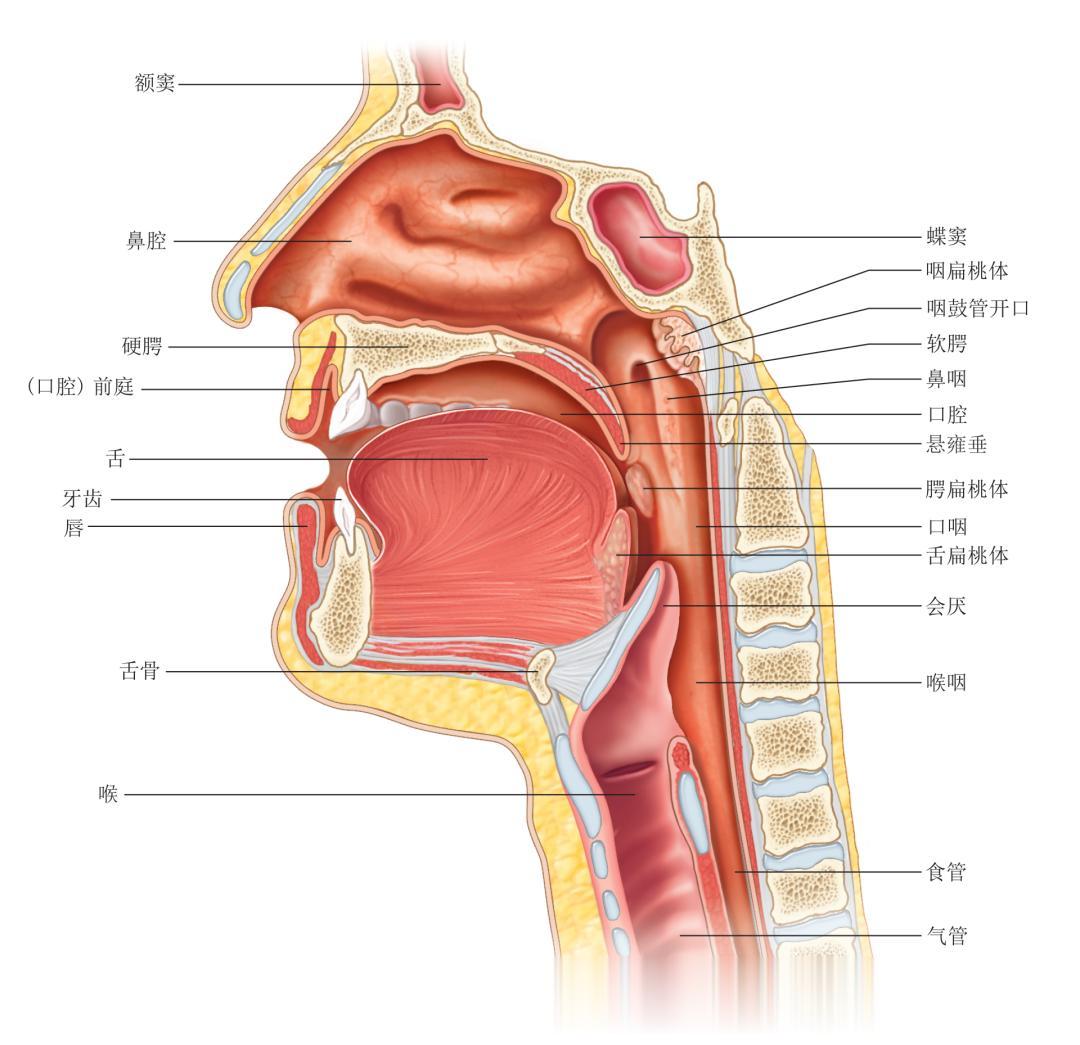

△ 口腔适合摄取食物并开始机械消化和化学消化。

△ 口腔、鼻腔和咽部的矢状切面